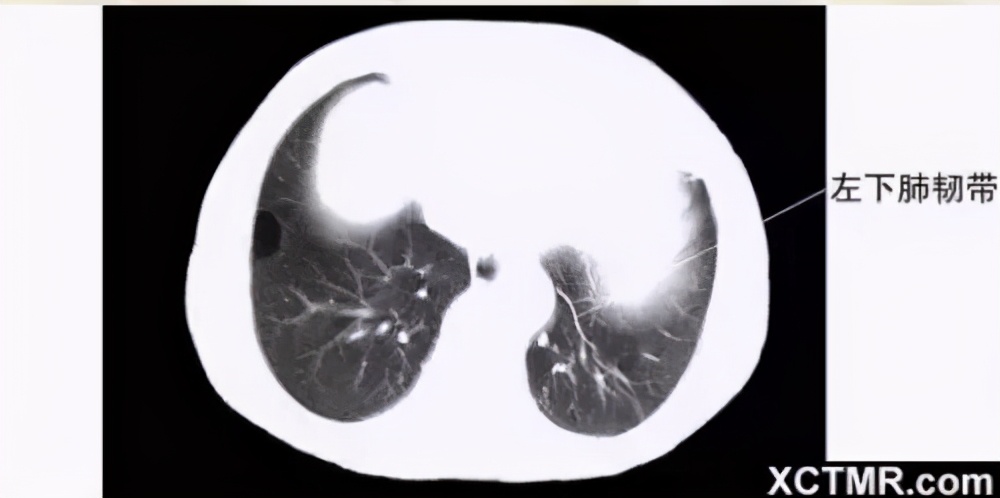

奇叶-奇静脉弓-胸膜分布